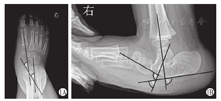

末次随访内容包括:①根据Adelaar评分系统[13]进行评分。其中临床评分包括:足外观不佳、踝关节于距下关节活动度丢失、距骨头突出、足内侧纵弓消失、后足外翻和穿特制矫形鞋;负重下影像学评分包括:异常距舟角、后足跖屈、距骨-跖骨轴线和距舟半脱位。②影像学测量(图1):负重下或模拟负重下前后位(anteroposterior,AP)跟距角(talocalcaneal angle, TCA)、TAMBA,及负重下或模拟负重下侧位(lateral,L)跟距角、胫骨跟骨角(tibiocalcaneal angle, TICAA)、距骨第一跖骨基底角X线片。

注:角1:前后位距骨-第一跖骨基底角;角2:前后位跟骨-距骨角;角3:侧位跟骨-距骨角;角4:侧位距骨-第一跖骨基底角;角5:侧位胫骨-跟骨角